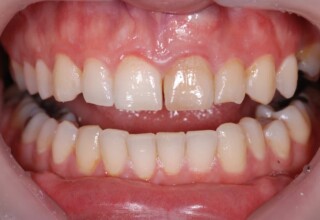

Restoration of bilateral diastemas between central and lateral incisors.

Diastemas were created mainly because of narrow laterals. After orthodontic treatment was finalized, the diastemas were closed with two composite resin restorations.